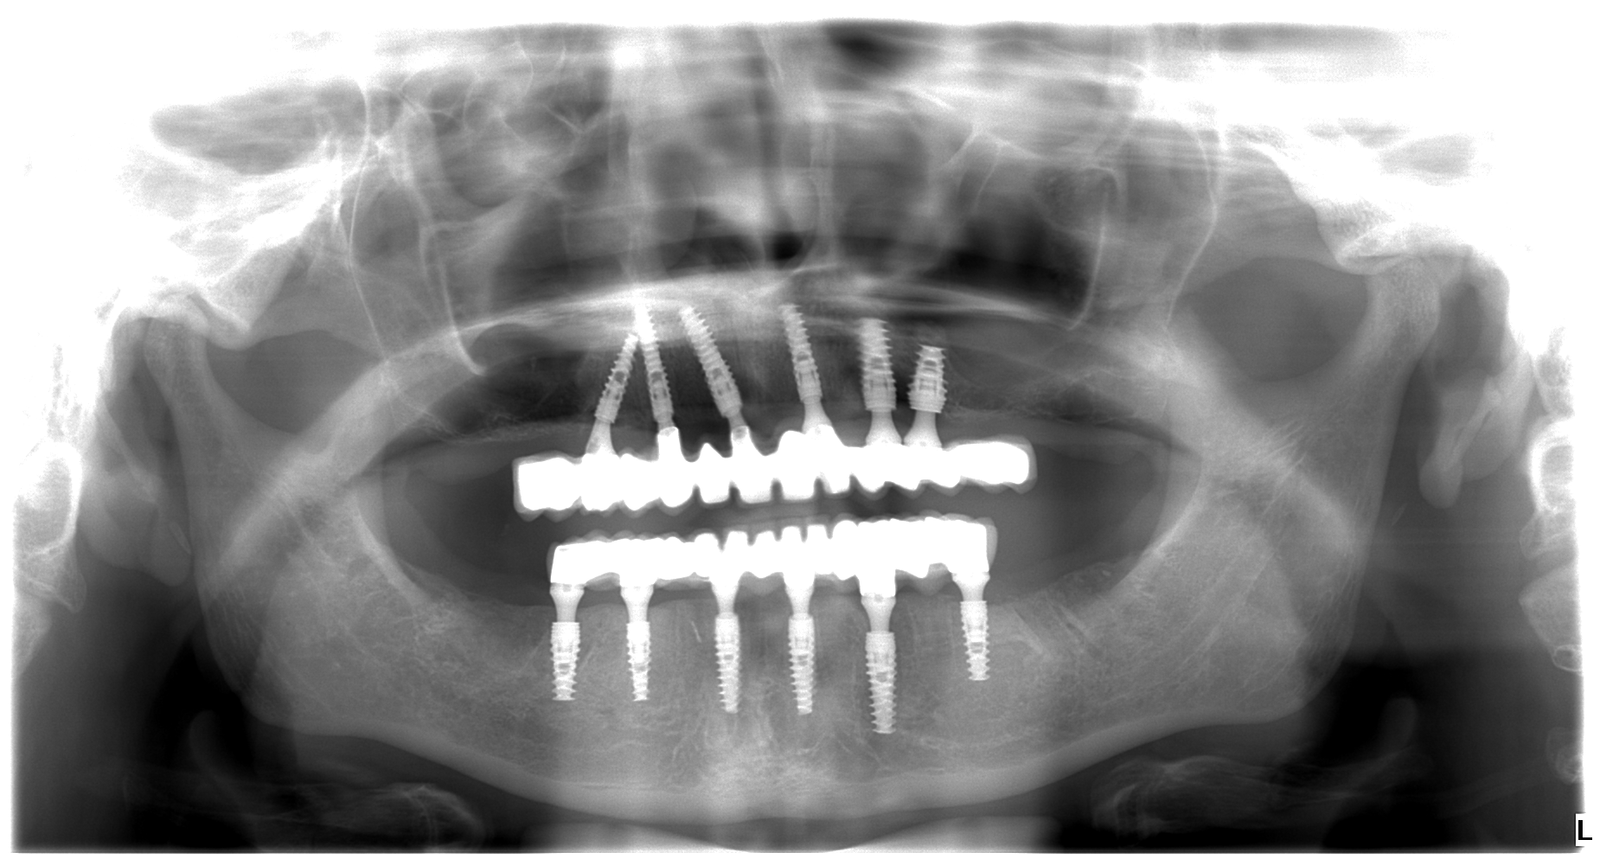

Adriana bola mladá žena, ktorá sa roky trápila s nekompletným a pokazeným chrupom. Hanbila sa smiať, vyhýbala sa foteniu a spoločnosti a spoločenským aktivitám. Rozhodla sa to zmeniť a prišla k nám. Po dôkladnej konzultácii, röntgene a 3D snímke sme jej navrhli plán na mieru: extrakcie nevyhovujúcich zubov, 6 implantátov hore, 6 dole a nový, 12-členný mostík do oboch čeľustí.

2. Zavedenie implantátov: Po extrakciách vám zavedú implantáty. Už počas hojenia získate dočasný mostík vystužený titánom – takže ani jediný deň nezostanete bez zubov.

3. Výroba finálneho mostíka: Po zahojení implantátov odoberieme presné odtlačky a vyrobíme keramické mostíky. Farbu a tvar zubov vyberáme spoločne, aby ste sa cítili prirodzene.